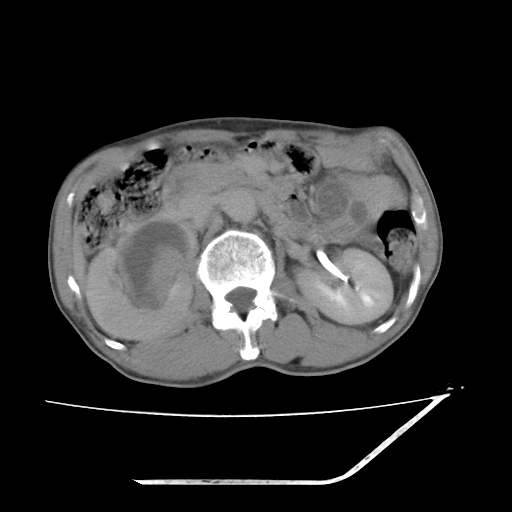

平扫

考虑右肾盂癌,肾动脉受侵,右肾功能减退,右肾盂输尿管积水,管壁增厚,考虑种植转移,应该把下面扫完的

支持右侧肾盂癌伴肾静脉瘤栓形成可能性大,右肾结石.肝右叶后段低密度影,不除外转移.

考虑右肾盂癌,肾动脉受侵,右肾功能减退,右肾盂输尿管积水,管壁增厚,考虑种植转移  支持

考虑右侧肾盂癌。右侧输尿管扩张未扫描完。

右肾盂旁ca并肾静脉瘤栓形成/肾功能降低。

右肾结石。

右肾盂癌,肾动脉受侵,右肾盂输尿管积水,管壁增厚,考虑种植转移

右肾盂移行细胞癌并右输尿管中段转移.肾积水.

1.右侧肾盂癌伴肾盂积水。

2.肾脏功能减退,原因有:(1)肾动脉受侵。(2)肾静脉受侵(3)肾积水,等。本例,肾动脉显影较好,但受压明显;肾静脉无明显显示,受压或静脉癌栓,下腔静脉腔内未见明显充盈缺损。

3.右侧上段输尿管扩张,原因:(1)积水所致;(2)种植。